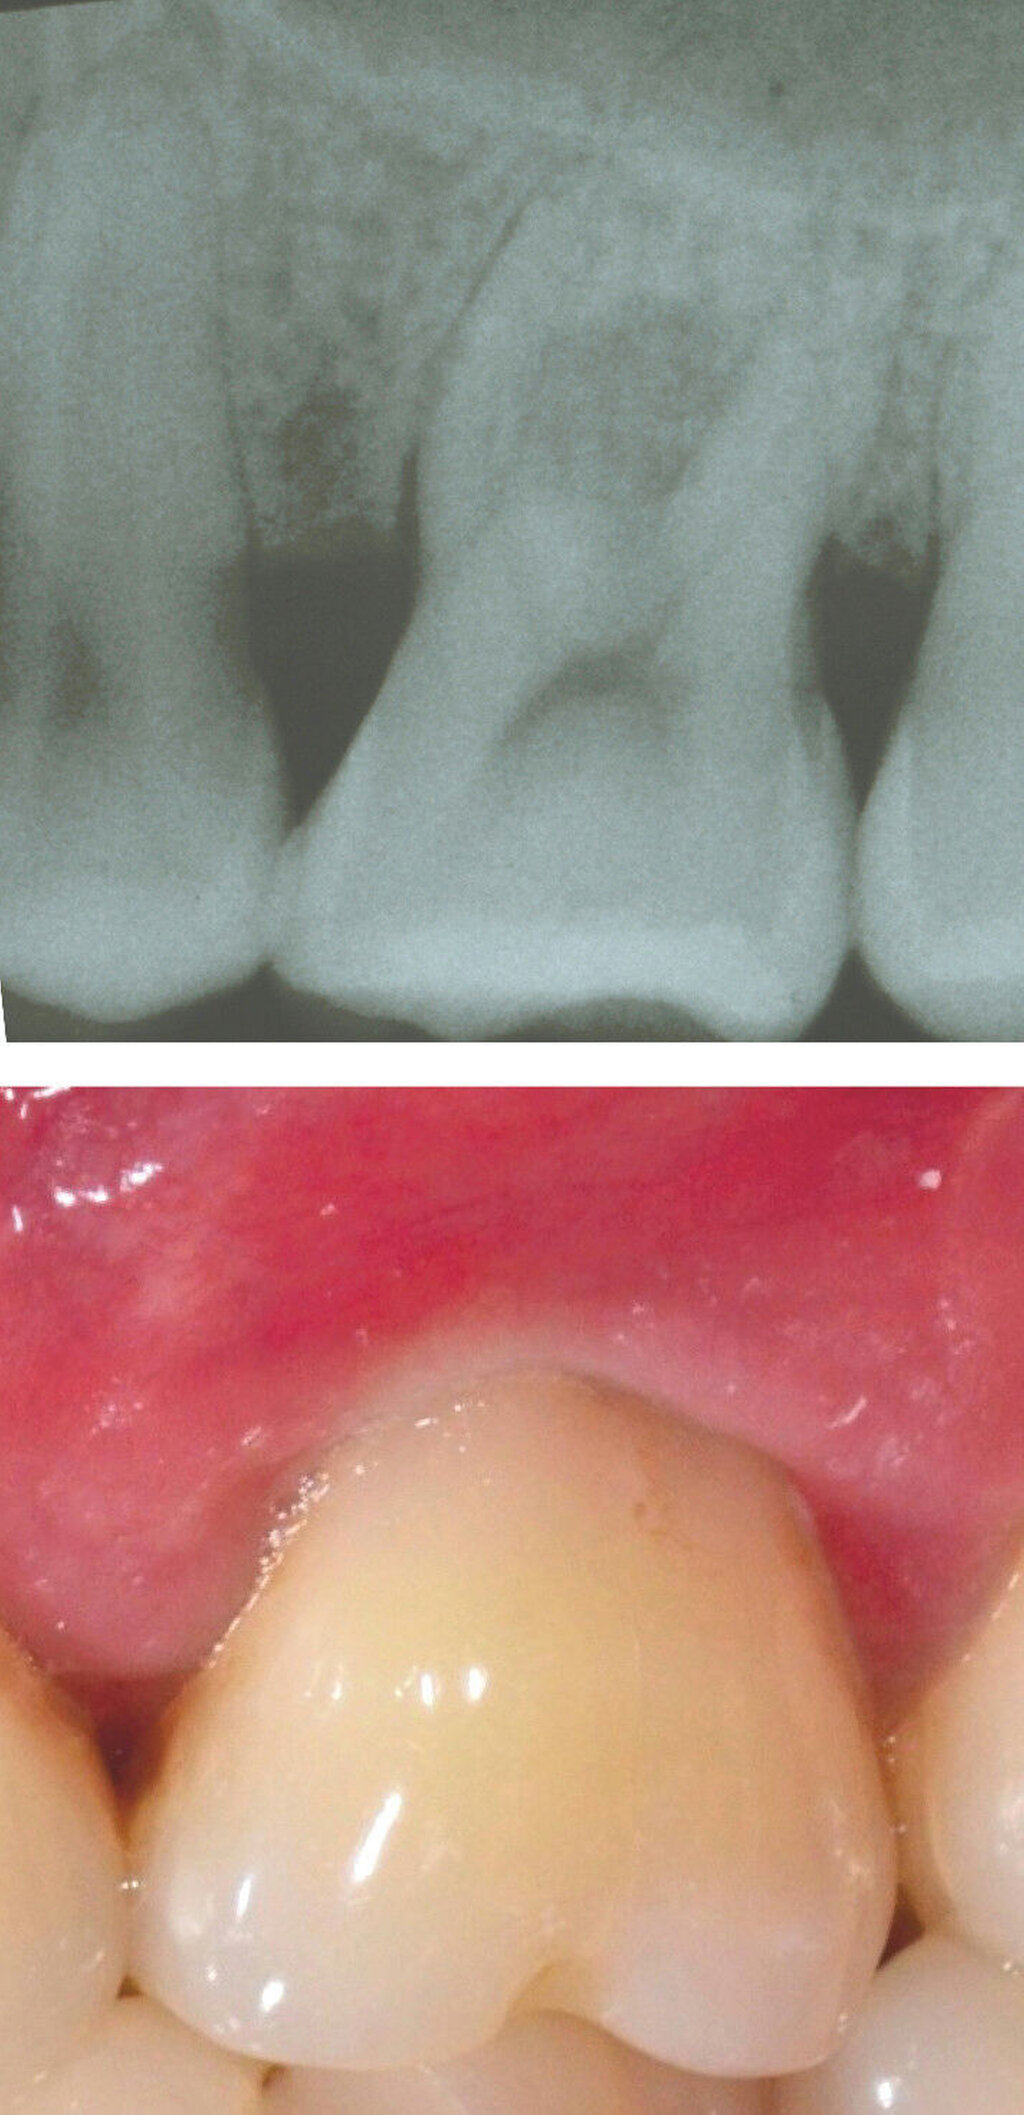

Systemische Faktoren, die den Erfolg regenerativer Maßnahmen beeinflussen können, sind beispielsweise ein unkontrollierter Diabetes oder eine eingeschränkte Immunabwehr. Verhaltensfaktoren wie Rauchen, unzureichende Mundhygiene und mangelnde Adhärenz müssen ebenfalls bei der Fallauswahl berücksichtigt werden. Zu den anatomischen beziehungsweise Defektfaktoren, die sich einigen Studien zufolge und nach Expertenkonsens negativ auf die Erfolgsaussichten einer regenerativen Furkationstherapie auswirken können, werden gezählt: ein erschwerter Zugang zum Operationsbereich, ein approximales Knochenniveau, das sich auf derselben Höhe oder sogar apikal des Furkationsdaches befindet, ein kurzer Wurzelstamm, ein enger Abstand zwischen den Wurzeln mit erschwerter Instrumentierung, eine deutlich erhöhte Zahnbeweglichkeit, ein dünner gingivaler Phänotyp, wenig keratinisiertes Gewebe, die Nähe eines Restaurationsrandes zum Furkationseingang und das Vorliegen einer gingivalen Rezession im Furkationsbereich.

Ein adäquater Zugang zum Operationsbereich und auch für die zukünftigen Mundhygienemaßnahmen ist äußerst wichtig. Molaren mit Grad-II-Furkationsdefekten (mandibulär und bukkal maxillär) sind Kandidaten, die für ein regeneratives Verfahren infrage kommen. Basierend auf der verfügbaren Evidenz sind interdentale Grad-II-Furkationsdefekte an Oberkiefermolaren deutlich weniger geeignet, höchstwahrscheinlich aufgrund des eingeschränkten Zugangs. Weitere lokale Charakteristika können Auswirkungen auf die Ergebnisse der regenerativen Furkationschirurgie haben. Zum Beispiel können ein dickerer Phänotyp und das Fehlen einer Weichgeweberezession die Heilung nach GTR-Verfahren positiv beeinflussen. Günstigere Ergebnisse sind an Stellen zu erwarten, an denen das verbleibende approximale Knochenniveau koronal zum Eingang beziehungsweise zum Dach des Furkationsdefekts liegt, verglichen mit solchen, bei denen das approximale Knochenniveau auf der Höhe oder apikal des Furkationseingangs liegt. Ein enger interradikulärer Abstand kann eine gründliche Defektinstrumentierung beeinträchtigen. Das Vorhandensein einer Wurzelkanalfüllung ist nicht per se eine Kontraindikation für die Furkationsregeneration – vorausgesetzt, es gibt keine Anzeichen für apikale pathologische Veränderungen.